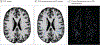

Main outcomes and measures: Individual PVS volume was calculated in the white matter of structural MRI. Cognitive impairment was based on neuropsychological assessment. Linear regression models were used to assess associations of PVS volume with neuropsychological assessments in former American football players. All analyses were adjusted for confounders associated with PVS volume.

Results: Analyses included 224 participants (median [IQR] age, 57 [51-65] years), with 170 male former football players (114 former professional athletes, 56 former collegiate athletes) and 54 male unexposed control participants. Former football players had larger PVS volume compared with the unexposed group (mean difference, 0.28 [95% CI, 0.00-0.56]; P = .05). Within the football group, PVS volume was associated with higher CHII-R (β = 2.71 × 10-8 [95% CI, 0.50 × 10-8 to 4.93 × 10-8]; P = .03) and CHII-G (β = 2.24 × 10-6 [95% CI, 0.35 × 10-6 to 4.13 × 10-6]; P = .03). Larger PVS volume was also associated with worse performance on cognitive functioning in former American football players (β = -0.74 [95% CI, -1.35 to -0.13]; P = .04).